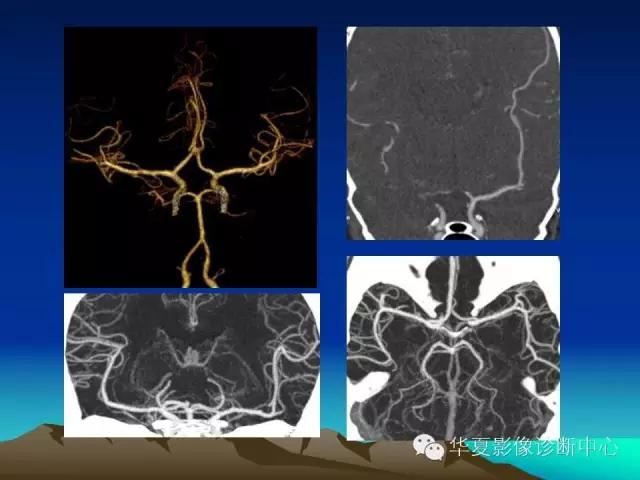

你不知道的脑血管解剖都在这里!